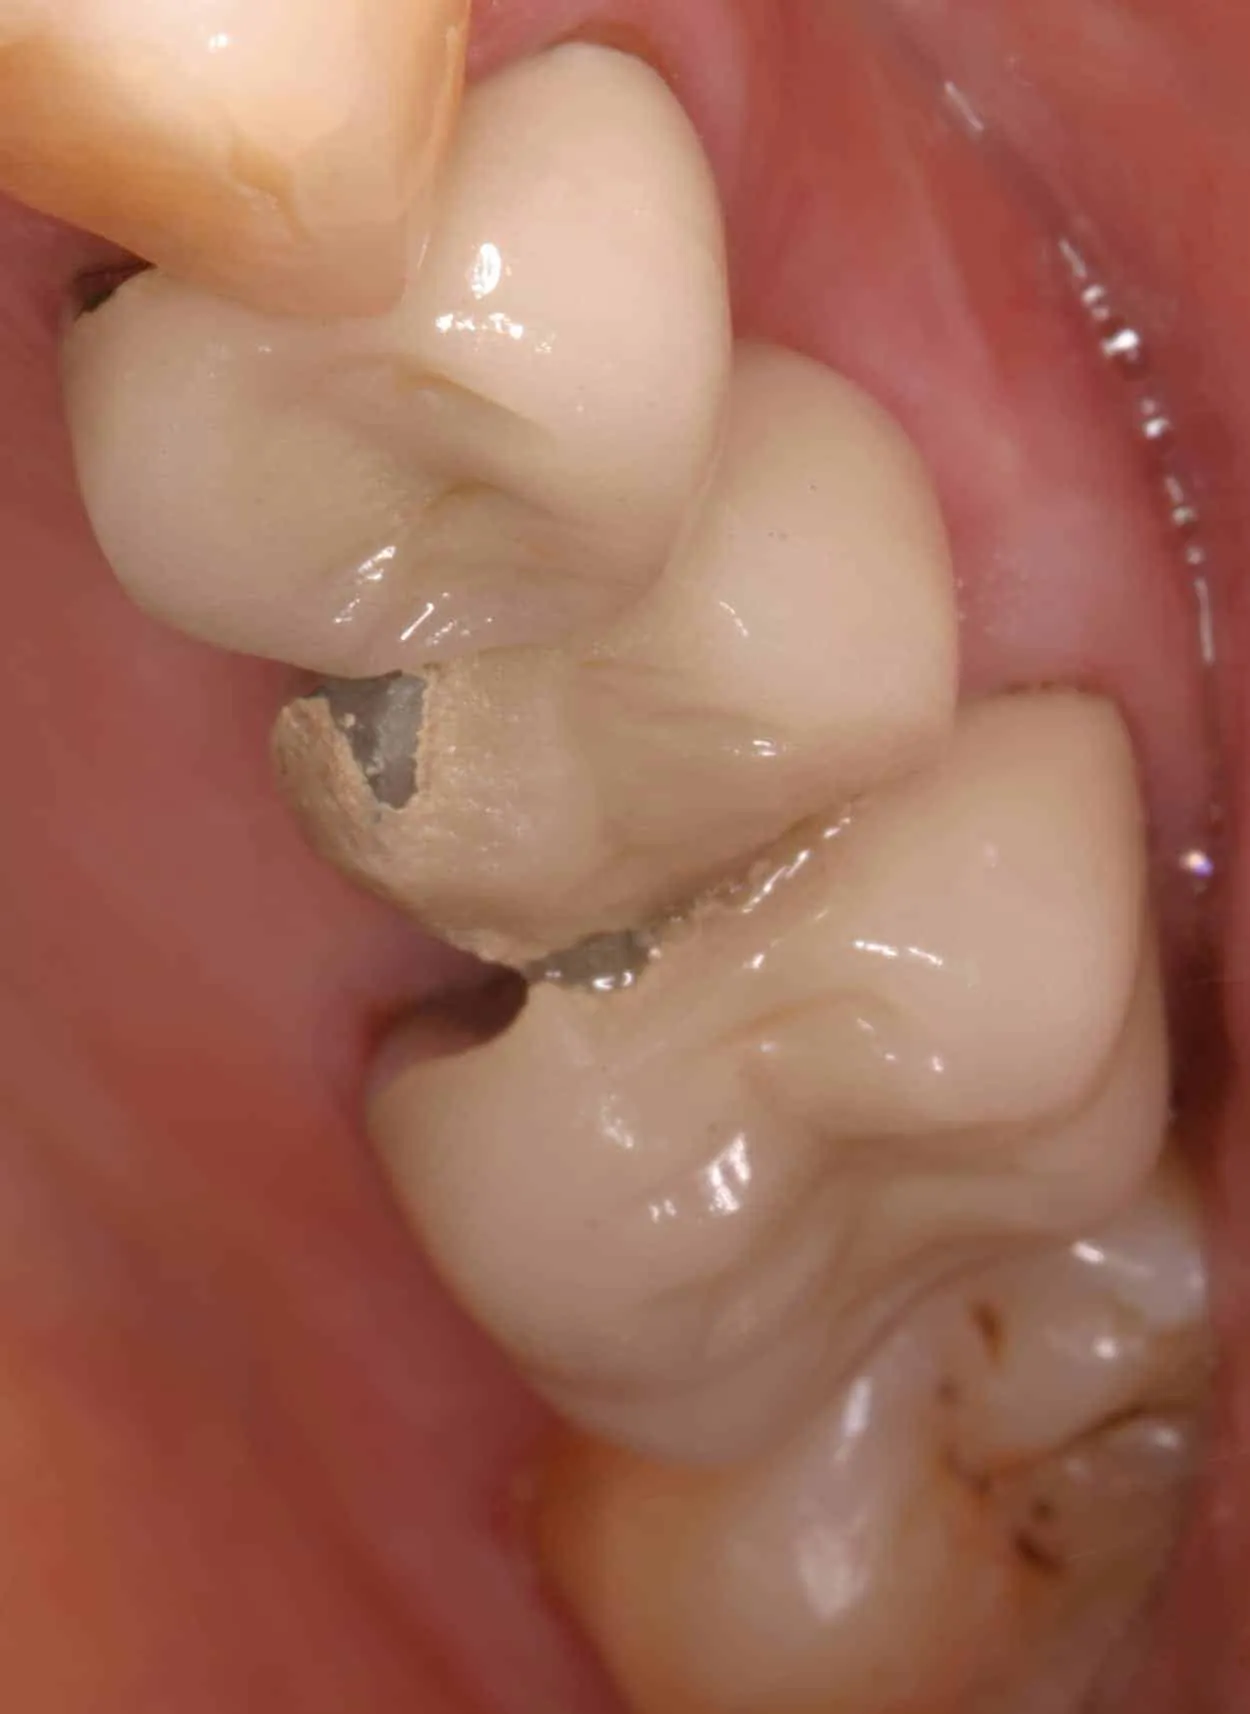

Before:Â Failed upper posterior three-unit bridge. Tooth #14 (upper left first molar) requires root canal therapy. Ideal candidate for a single dental implant to replace missing tooth #13 (upper left second premolar) and two single crowns on abutment/support teeth 12 (upper left first premolar) and 14. However, the patient is not interested in implant therapy and would like revision crown and bridge (fixed partial denture) therapy.

After:Â Revision crown and bridge therapy. Tooth #14 was carious and required root canal therapy and a build-up (foundation restoration) prior to definitive bridge therapy. Three-unit fixed partial denture (bridge), porcelain fused to gold, abutment teeth 12 and 14.